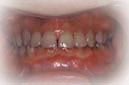

治療前の状態です。

上の前歯に乱杭いがあり、八重歯になっています